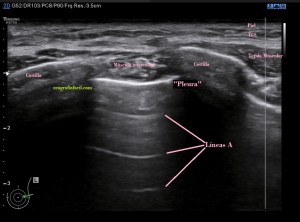

250. Ecografía de Tórax, Líneas A y B.

Llevaba tanto tiempo queriendo explicar esto…Hoy voy a tratar de explicarte de forma muy sencilla y sin meterme en muchos jardines, cómo debes ver un patrón aéreo normal en una exploración de tórax o en aquellas exploraciones donde el pulmón pueda ser valorado, por ejemplo en la ecografía de mama.

Bueno, vamos a lío. ¿La pleura se puede estudiar con ecografía?. Es una pregunta complicada, como órgano medible o cuantificable con el caliper de nuestros equipos, la respuesta es no. La imagen hiperecogénica que ves entre los arcos costales y a la que denominamos erróneamente «Pleura» deslizándose, es un artefacto especular producido por la reflexión de más o menos de un 99% de los ecos que vuelven al transductor debido a la interfase tan potente resultante de la parte blanda de la pared torácica y el aire del pulmón.

El movimiento de esa línea hiperecogénica se conoce como Sliding pleural o Lung Sliding ( vídeo enlace a instagram). Se debe al desplazamiento de la pleura parietal y la visceral. Si este desplazamiento no se produjese, existirían figuras patológicas a valorar pertinentemente. Por tanto, la pleura, como tal, no es valorable, sí lo es los signos ecográficos que nos hablan de normalidad o no normalidad en esta localización.

Si el pulmón está aireado y sano vamos a ver esta imagen:

1. Líneas A

Líneas A. En la imagen 1 puedes ver la normalidad de un pulmón bien aireado en esa región explorada. La anatomía radiológica, la imagen hiperecogénica que asociamos a la pleura y los artefactos en espejo de las tres líneas A paralelas a la línea que hemos denominado «Pleura» y que tan solo es la primera de las líneas especulares, es decir, artefacto de espejo que se produce entre la pared torácica y el aire del pulmón.

Es un error en la lectura de los ecos de retorno, me explico, cuando el haz llega a la estructura y vuelven al transductor lo hacen apropiadamente, pero hay otra parte del haz que llega a la siguiente capa hiperecogénica, que devuelve ecos que chocan contra la parte posterior de la primera interfase hiperecogénica, estos ecos tardan más en llegar al transductor y por tanto hace que parezca que está más profundo, es para explicarlo muy básicamente, una doble lectura en tiempos distintos. En ecografía el tiempo de lectura equivale a profundidad, por tanto la segunda lectura del objeto será incongruente y ocasiona esta falsa imagen en planos profundos.

En conclusión, la líneas A son de NORMALIDAD. Son hiperecogénicas, lineales, paralelas  horizontalmente y equidistantes.

Si por el contrario, viésemos esta imagen…

2. Líneas B

Líneas B. Detalle.

Líneas B.Esta visualización del espacio intercostal indica Líneas B (flechas rosas), patología de diversa índole, normalmente, por la pérdida de la aireación normal en el contexto del síndrome intersticial y la presencia de tejido inflamatorio y/o líquido en esa región del pulmón que permite el paso de los trenes de ultrasonidos produciendo este tipo de imagen que es también otro artefacto, esta vez en cola de cometa.

Este artefacto aparece cuando el haz de ultrasonidos choca contra una interfase estrecha y muy ecogénica apareciendo detrás de esta interfase una serie de ecos lineales.

El aspecto de una línea B es lineal, perpendicular, hiperecogénica. Ojo, estas líneas pueden aparecer en «normalidad», pero cuando son únicas, cuando son 3 o más en un mismo espacio intercostal, deben saltarnos las alarmas, son una línea roja que debemos comunicar a la radióloga, para que eventualmente la paciente o el paciente se evaluado con otras técnicas.

En una zona donde hay Líneas B no puede haber Neumotórax.

Nota Importante: Las líneas A y B, además de aparecer en la pantalla tienen que cumplir una serie de requisitos para que sean consideradas como tales, como pueden ser en el caso de las líneas B, que aparezcan en un número por encima de 3 y que además esas líneas verticales lleguen hasta la profundidad de la pantalla.